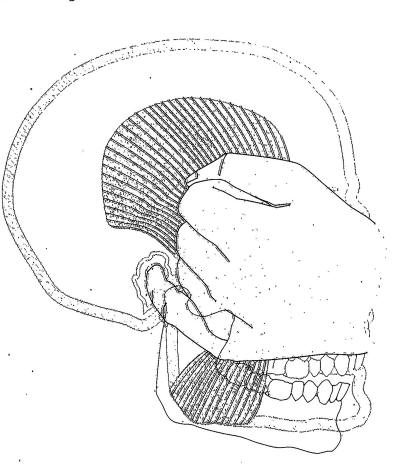

Palpación del músculo masetero: |

La palpación del músculo masetero no presenta

inconvenientes, con una presión moderada en apertura y

cierre podremos determinar el grado de dolor que presenta el

paciente y el trismus presente. |